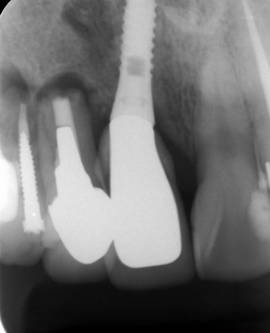

治療後。歯周病で失われた骨が回復しています。使用インプラントはスプラインツイストです。

インプラント装着後6年。順調に経過しています。12か月毎のメインテナンスをしています。